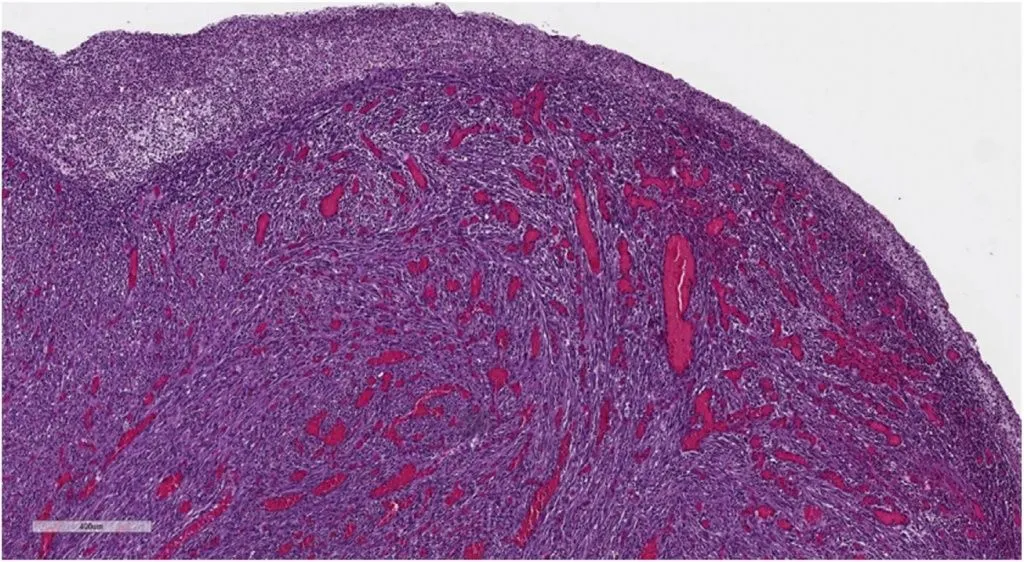

Микроскопическое исследование новообразования показало мезенхимальную пролиферацию, состоящую из веретенообразных клеток — мономорфных и без значительной атипии, организованных в пучки, ассоциированных с диффузной лимфоцитарной инфильтрацией, плазматическими клетками и эозинофилами, распространяющимися на слизистую оболочку и инфильтрирующими подслизистую оболочку (рис. 3, 4).

Рисунок 3 [1].

Рисунок 4 [1].

При иммуногистохимическом исследовании: положительно для SMA, отрицательно для цитокератина, десмин, S-100, Мелан-А, CD34, CD117, DOG-1, CD21, CD23, CD1a и ALK. На основании этих результатов диагноз IMT был подтвержден.